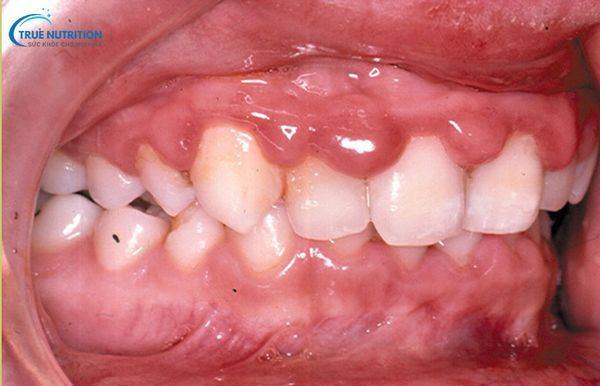

Hình Ảnh Viêm Nướu Răng

Hình ảnh minh họa các triệu chứng phổ biến:

- Nướu sưng đỏ: Đây là dấu hiệu viêm cấp tính, thường kèm theo cảm giác đau nhức và khó chịu.

- Viêm chân răng, có chảy máu: Xuất hiện khi vệ sinh răng miệng không đúng cách, khiến vi khuẩn tấn công sâu vào mô nướu.

- Nướu có mủ, tụt lợi: Biểu hiện của viêm nặng, thường đi kèm với mùi hôi miệng khó chịu và cần can thiệp y khoa khẩn cấp.

- Viêm nướu ở răng hàm trên/hàm dưới: Các vùng răng chịu lực lớn dễ bị tổn thương, gây ảnh hưởng đến khả năng ăn nhai.